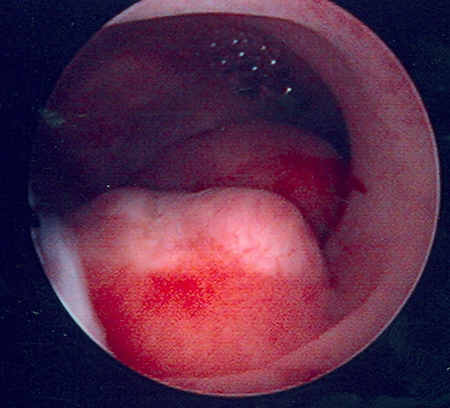

Hysteroscopic examination of the uterine cavity demonstrates the presence of two contiguous submucous uterine fibroids in this patient with persistent heavy menstrual bleeding

From the personal collection of Dr M.F. Mitwally and Dr R.J. Fischer; used with permission